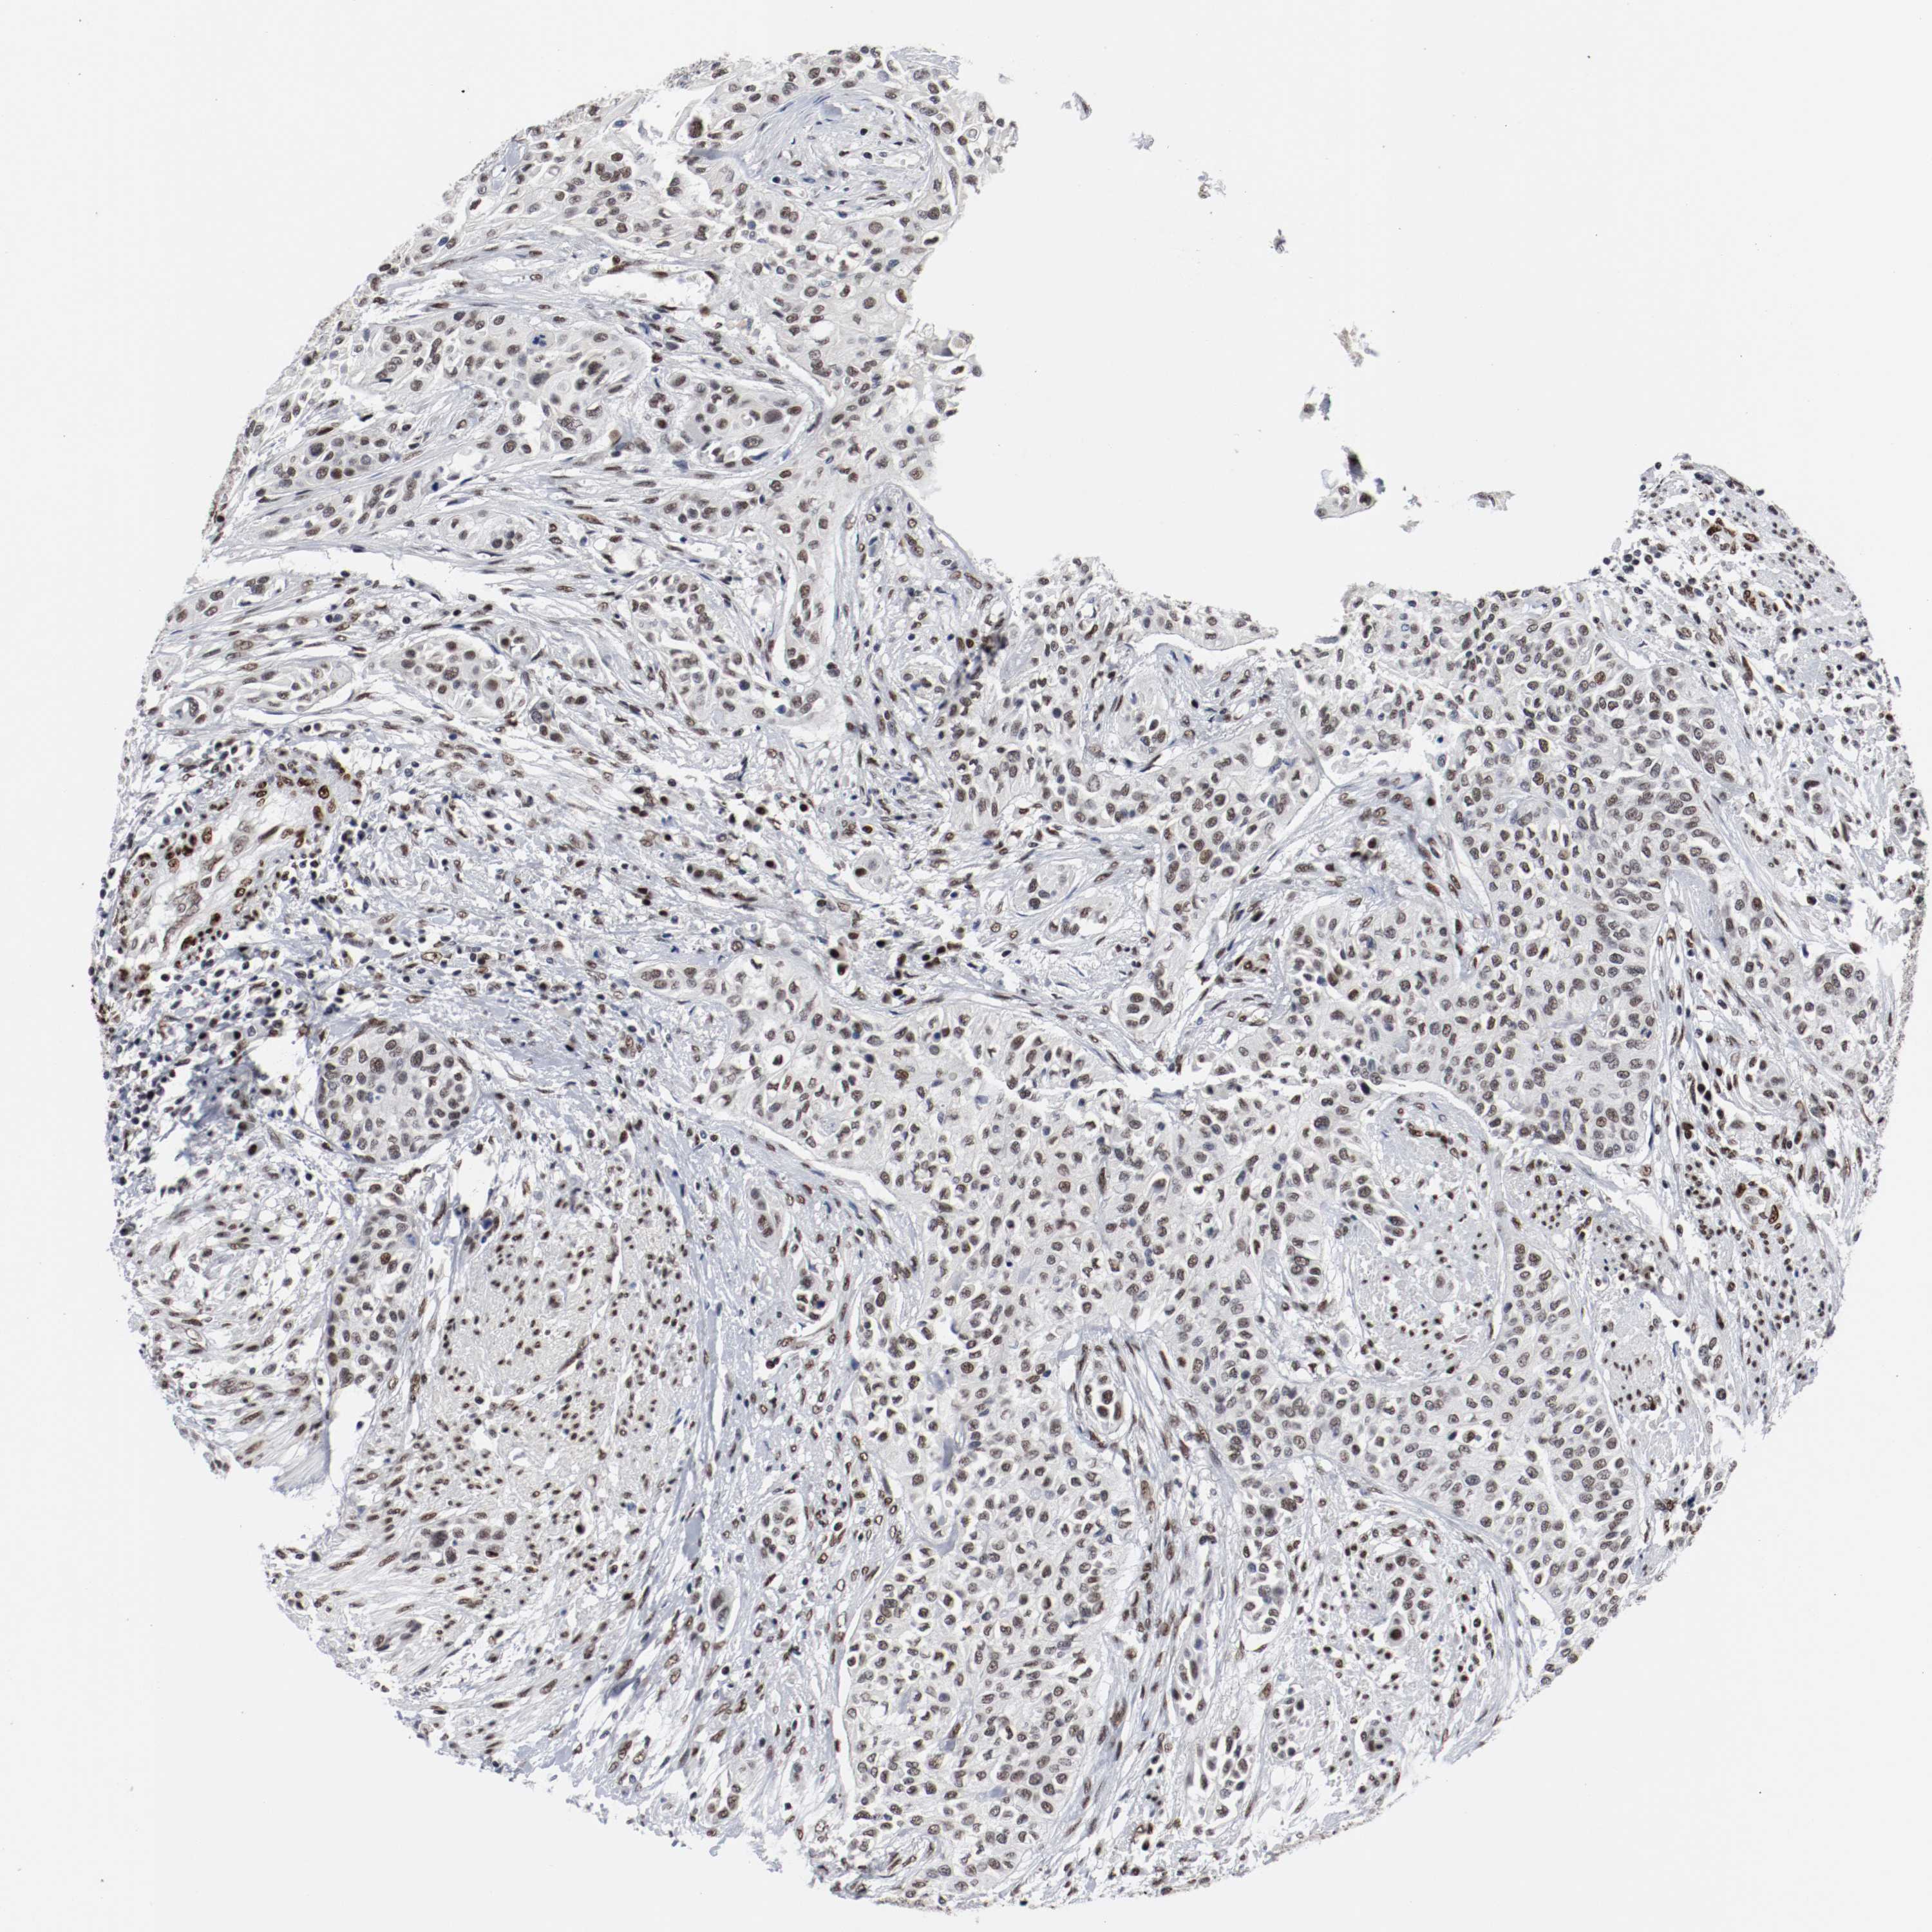

UROTHELIAL CANCER - Protein expressioni

A mouse-over function shows sample information and annotation data. Click on an image to view it in a full screen mode. Samples can be filtered based on level of antibody staining by selecting one or several of the following categories: high, medium, low and not detected. The assay and annotation is described here.

Antibody stainingi

Antibody staining in the annotated cell types in the current human tissue is reported as not detected, low, medium, or high, based on conventional immunohistochemistry profiling in selected tissues. This score is based on the combination of the staining intensity and fraction of stained cells.

Each image is clickable and will lead to virtual microscopy that enables deeper exploration of all samples and also displays staining intensity scores, fraction scores and subcellular localization as well as patient and tissue information for each sample.

Antibody HPA004807

Antibody HPA007114

Staining

High

Medium

Low

Not detected

Intensity

Strong

Moderate

Weak

Negative

Quantity

>75%

75%-25%

<25%

None

Location

Nuclear

Cytoplasmic/membranous

Cytoplasmic/membranous,nuclear

Urothelial carcinoma, High grade

Urothelial carcinoma, Low grade